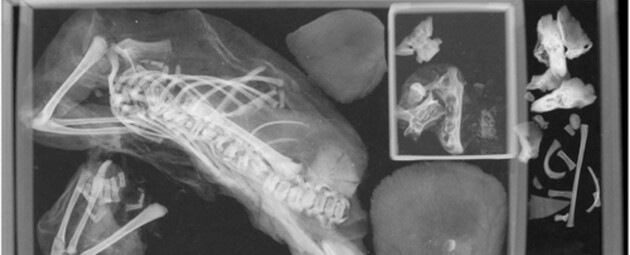

Более 100 лет останки находились в коллекции Смитсоновского музея. Но Марголис решила исследовать их подробнее. Она провела КТ-сканирование останков девушки, чтобы подтвердить причину ее смерти. Вместо этого она обнаружила нечто неожиданное.

В области груди Марголис заметила объекты, которые не принадлежали мумифицированному плоду. Марголис и антрополог из Университета Джорджа Вашингтона Дэвид Хант исследовали рентгеновские снимки останков и с удивлением обнаружили второй плод.

Вероятно, перемещение плода произошло, когда мать бальзамировали. Диафрагма и соединительные ткани растворились, что позволило ему перемещаться внутри тела женщины.